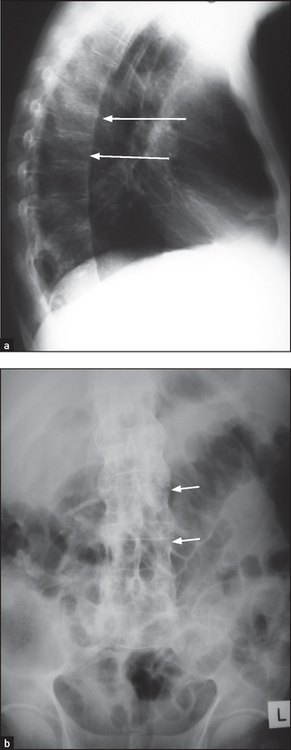

Figure 26.4 Ankylosing spondylitis Anteroposterior (a) and lateral (b) X-rays of the thoracic spine showing ankylosis of the sacroiliac joints, extensive syndesmophyte formation (short arrows) and squaring of the vertebral bodies (long arrows).

X-rays of the spine and sacroiliac joints (see Figure 26.4) may show ankylosis (fusion) of the sacroiliac joints and ‘squaring’ of the vertebral bodies as a result of loss of their anterior corners and periostitis of their waists. ‘Bridging syndesmophytes’a occur as a result of ossification of the fibres of the joint annulus. Severe disease causes the changes called bamboo spine visible on X-ray.